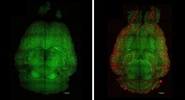

После трех инъекций наночастиц уровень амилоида в мозге мышей снизился на 50–60 процентов всего за час, а спустя несколько месяцев животные полностью восстановили когнитивные функции.Lenta.ru

Исследователи использовали генетически измененных мышей, у которых развивалась форма болезни Альцгеймера.РЕН ТВ